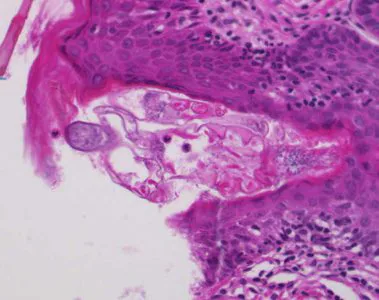

Sarcoptes scabiei mites in tissue specimens.